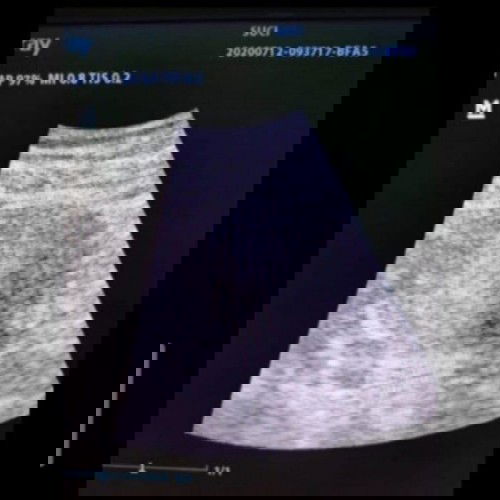

Hai semua yang kebetulan gak sengaja lihat postingan ini. Aku mau berbagi pengalamanku yang barangkali ada diantara kalian yang sedang, atau pernah mengalami juga. Jadi, aku program hamil mandiri dengan ovulation test strip. HPHTku tanggal 5-Juni-2020. Namun masa suburku baru datang tanggal 24-Juni-2020. Dan atas rezeki Allah program hamilku berhasil, testpack menunjukan dua garis samar ditanggal 5-Juli-2020. Dan aku memutuskan untuk USG sedini mungkin ditanggal 12-Juli-2020 untuk memastikan kehamilan. Tapi saat USG, jangankan Janin yang aku bayangkan akan terlihat, kantung kehamilan pun tidak terlihat pada saat itu. (lebih tepatnya belum terlihat karena masih terlalu dini ☺️) Yang terlihat malah kista hormon seukuran 0,5 cm, sangat amat kecil dan kata dokter tidak perlu dikhawatirkan karena akan kalah dengan bayinya. Pulang dengan rasa khawatir, sedikit kecewa karena ekspektasi sendiri yang terlalu tinggi. Dan akhirnya sempat down, karena seharusnya kantung kehamilan dan janin sudah terlihat kalau dihitung dari HPHT. Tapi teringat saat dokter memberikan semangat dan berkata mungkin karena faktor pembuahan baru saja terjadi/baru mulai proses, mengingat berdasarkan test ovulasi, masa subur baru terjadi ditanggal 24-Juni-2020. Jadi mungkin usia kandunganku belum genap 2 minggu. Lalu aku lanjutkan minum asam folat, es krim, dan susu hamil. Sampai akhirnya, dihari ini tepat tanggal 29-Agustus-2020. Aku dan suami dapat melihat kantung kehamilan dan janin yang lincah menendang-nendang. Alhamdulillah... 😭❤️ Ditambah dengan terlihatnya detak jantung halus dari janin di layar monitor ❤️ Semoga dengan aku menceritakan pengalaman ini para calon Ibu yang sedang sedih/kefikiran karena masalah yang sama bisa menjadi lebih tenang, aamiin. - S ❤️ #BerbagiCerita #berbagiceritabahagia #KantungJanin #KantungKehamilan #KantungHamil #KantungJanin